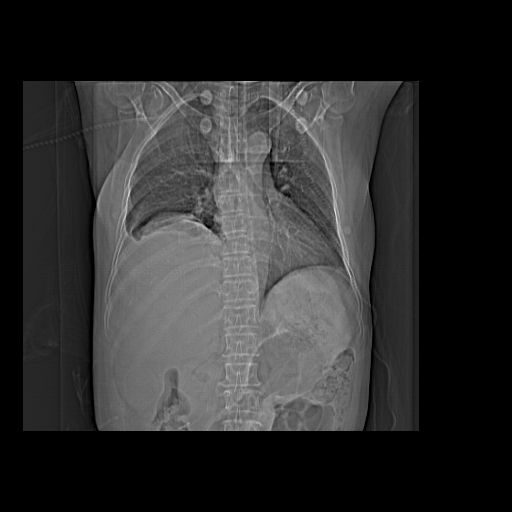

以下是引用dyqct在2006-12-7 21:08:00的发言:[br]考虑:1、肝内外胆管多发性结石伴肝左叶外侧段肝萎缩;[br] 2、右膈下多发脓肿;[br] 3、右侧少量胸腔积液、斜裂积液;[br] 4、左肾囊肿。

以下是引用jiazh在2006-12-7 20:37:00的发言:[br]肝脏周围半狐形低密度影,肝脏表面受压推移,考虑膈下脓肿可能性大;2、右侧胸腔积液

以下是引用拾荒者在2006-12-7 21:44:00的发言:[br]肝内外胆管多发结石,右膈下多发脓肿,右胸膜腔及叶间裂积液,左肾囊肿。[br] [br]